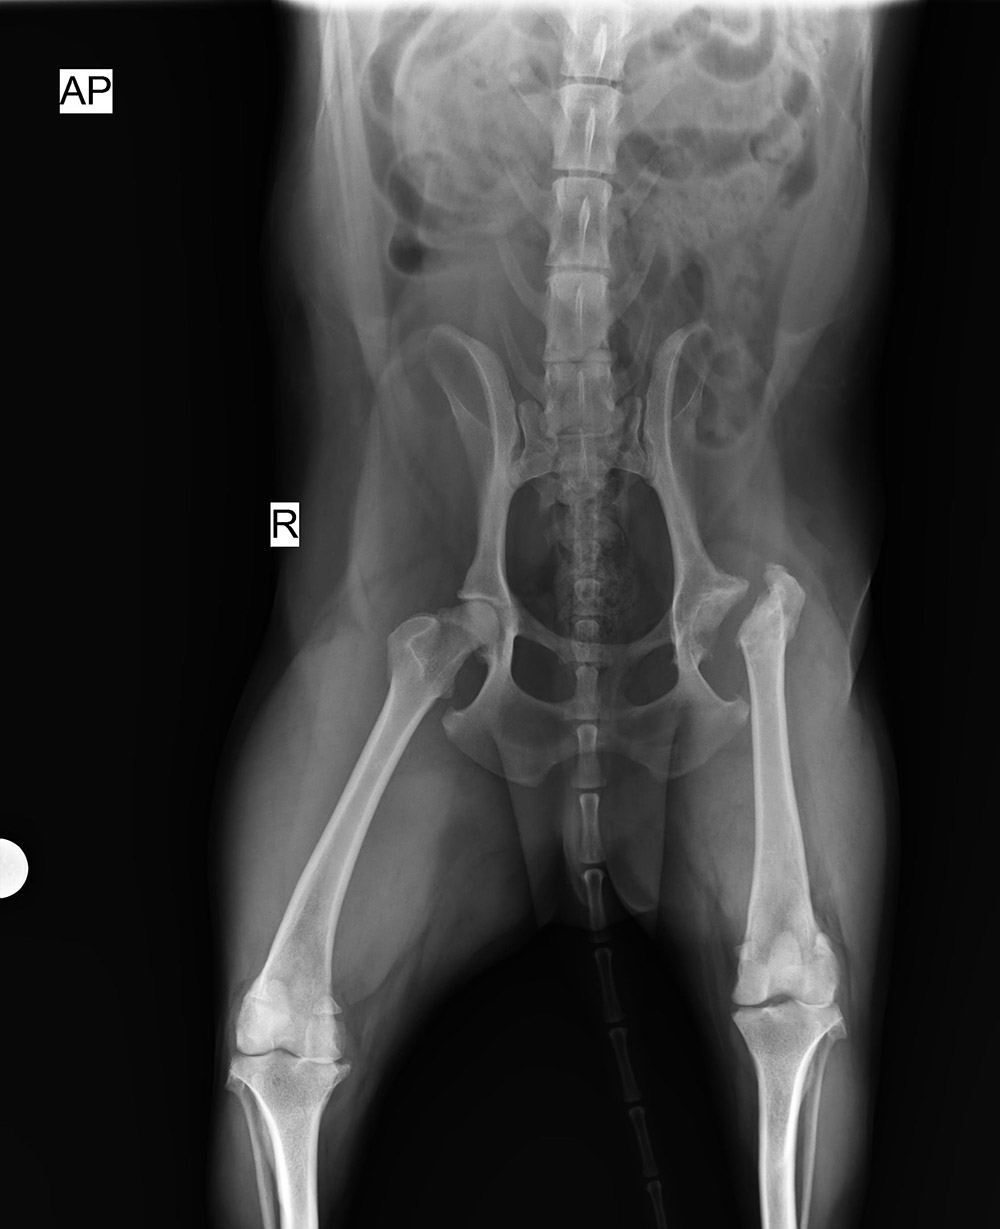

北京愛瑞可動物醫(yī)院

2016/5/31